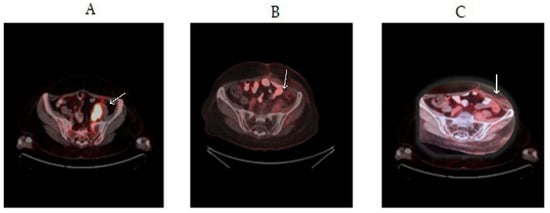

| Our present case-study | Mixed-type ovarian cancer | PIK3CA (E542K) | Oral 2 × 200 mg/day alpelisib. | CR (complete response) over 2 years. |